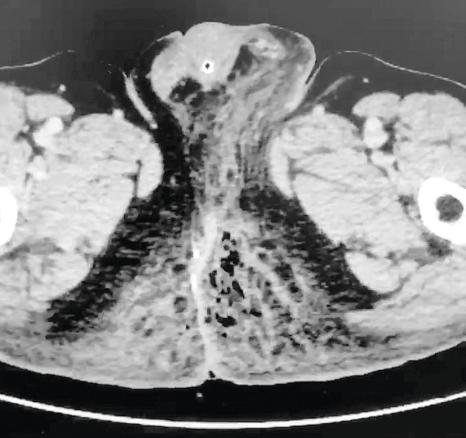

Un homme de 45 ans, diabétique, consulte aux urgences pour une douleur anale, pour laquelle il prend des anti-inflammatoires non stéroïdiens (AINS) depuis quatre jours. À l’examen, un érythème des deux fesses s’étend vers le scrotum (fig. 1).